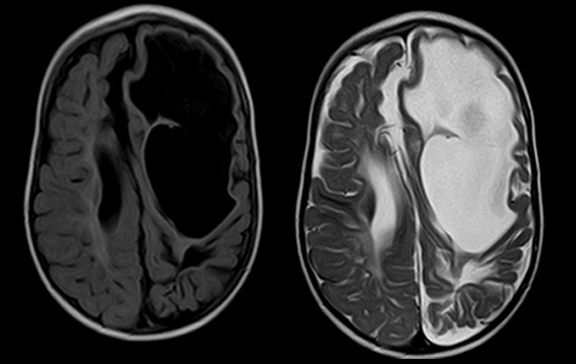

Magnetic resonance imaging of brain. Axial images of porencephalic cyst on left frontoparietal region connected with the ipsilateral lateral ventricle (Page 620)